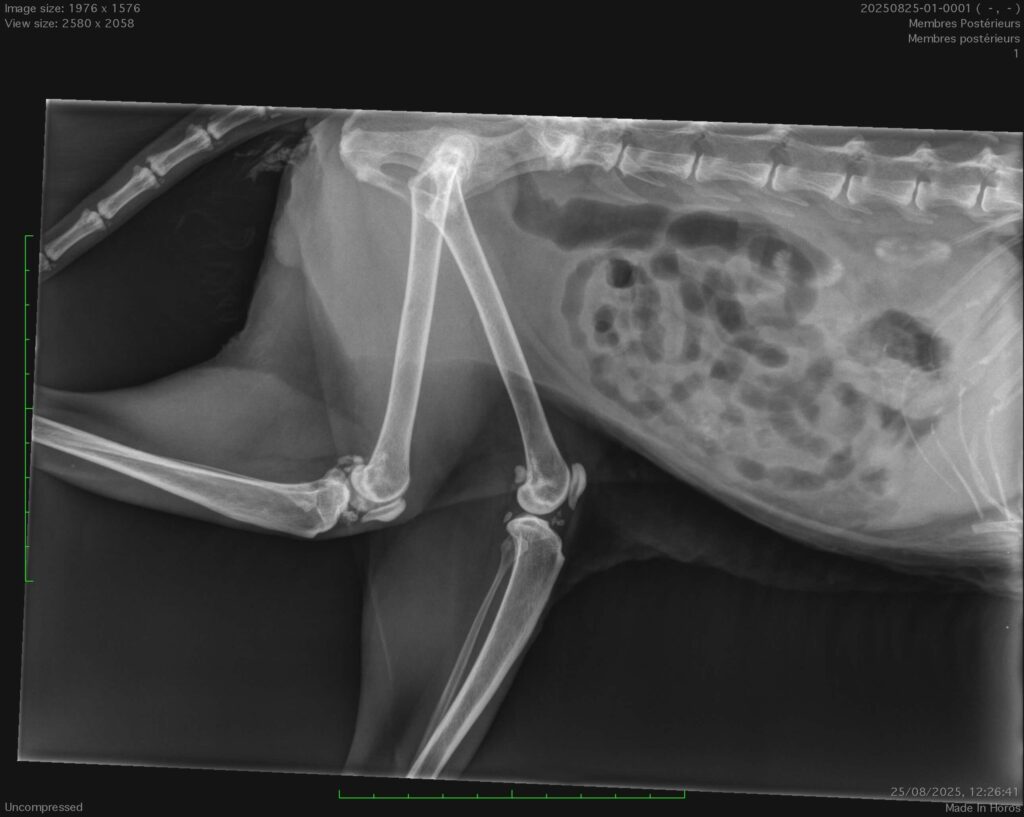

Radio d’un chat de 19 ans qui a des difficultés locomotrices, ne sait plus monter les escaliers . La radio montre une arthrose sévère des deux genoux qui engendre de la douleur.Il ne sait plus aller dans un studio à l’étage où il se sentait protégé. Cela l’angoisse fortement, il miaule, n’est plus propre. Il est important de traiter cette douleur et d’aménager son environnement pour son bien-être physique et moral